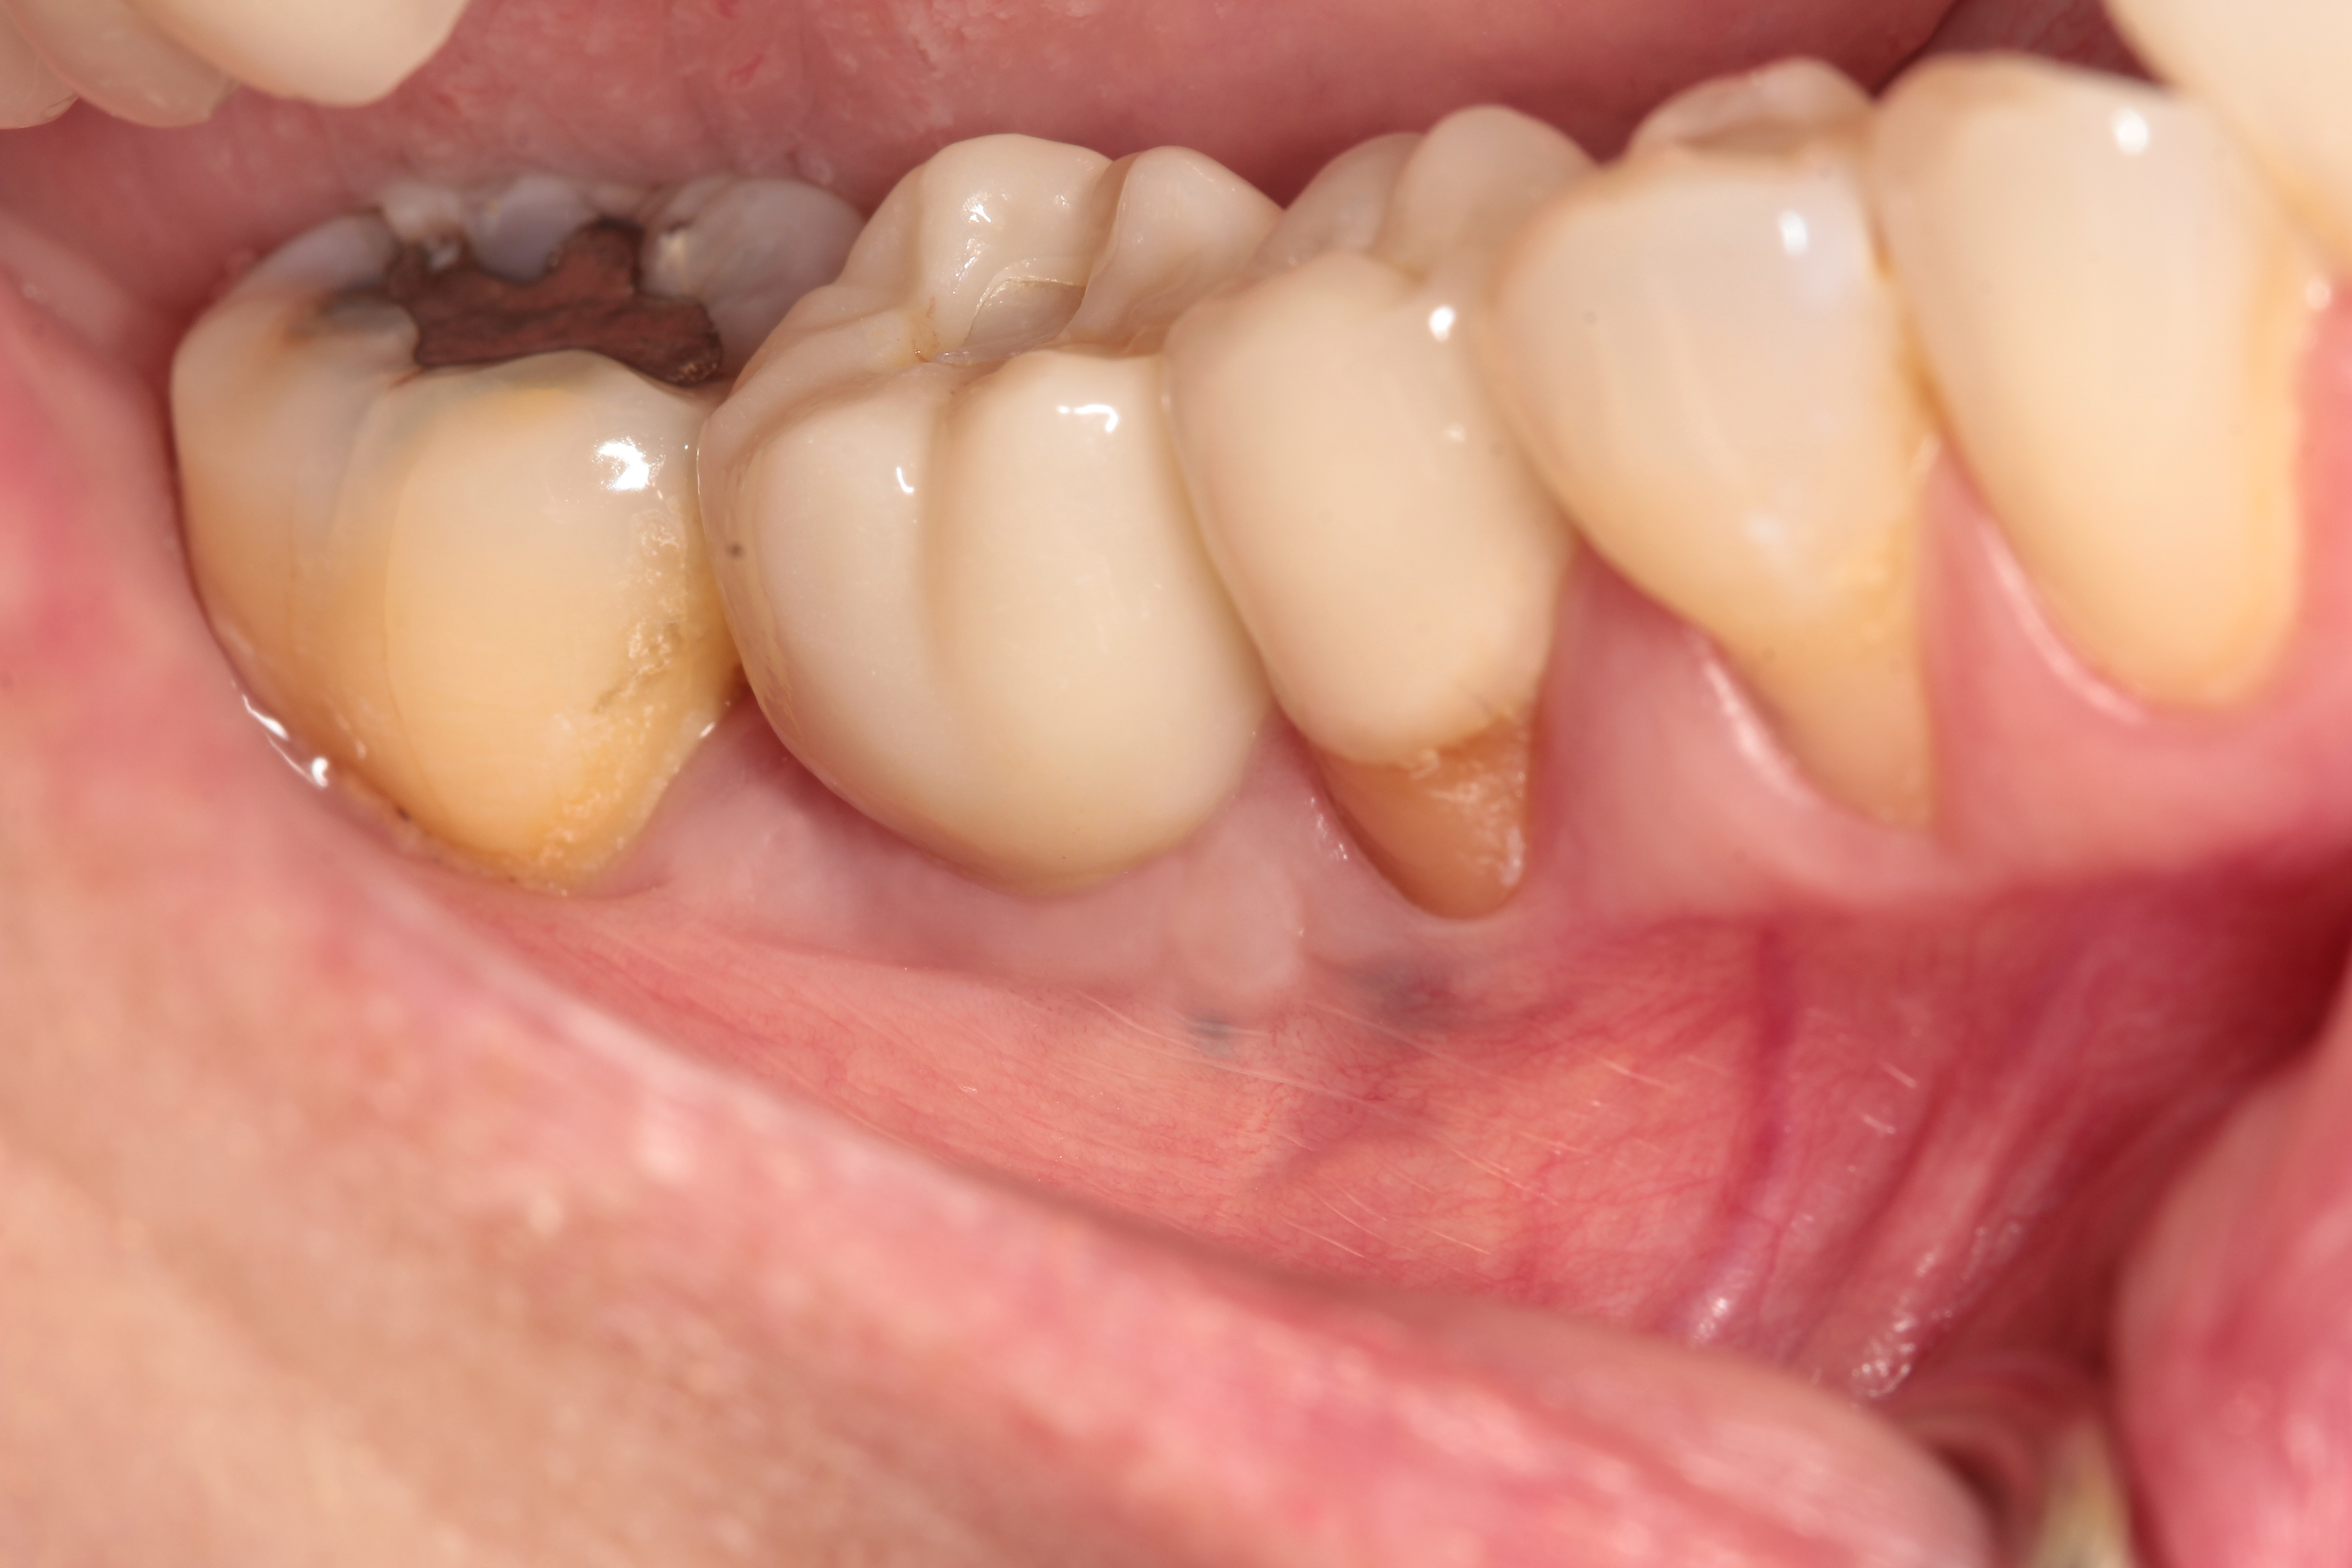

Fig 5. Example of an implant that is placed too shallow, such that the emergence profile of the implant crown cannot be made to an ideal profile, leading to potential food trap issues.

Figure 5